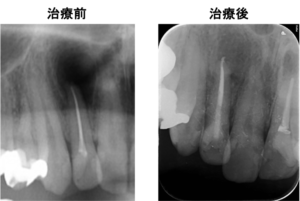

今回は、右上の前歯の歯茎から膿が出た状態の歯の根に対して根管治療を行った症例をご紹介致します。

右上2番の歯の根の先に炎症があり膿が出ていたので、しっかりとした根の治療(精密根管治療)を提案し、患者様の合意を頂き治療を行うこととなりました。

左図のレントゲン写真では右上2番の根の先に炎症があり大きく骨が溶けている部分があります(矢印部) 。

治療前後